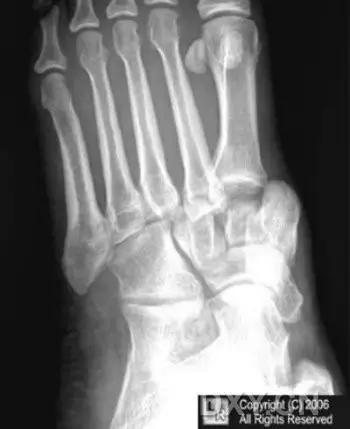

13. Lisfranc 骨折

骨折累及到足的跗骨关节。跖跗关节位于足的前部,是构成足纵弓及横弓的重要结构。

第一跖骨与第一楔骨组成鞍状关节,整个跖跗关节的稳定性,有赖于第一跖跗关节的稳定性,一旦第一跖跗关节发生脱位,其他 4 个跖跗关节容易发生脱位。第一跖跗关节的关节囊有背侧和跖侧副韧带增强,其内缘尚有胫前肌腱附着。第一、二跖骨基部无韧带相连,第一楔骨与第二跖骨基部间有坚韧的 Lisfranc 韧带相连,有助于第一跖跗关节的稳定性。第二楔骨较短,第二跖骨位于第一、二楔骨之间成为外力作用的支点。因此第二跖骨基底易发生骨折。

Lisfranc 关节复合体(Lisfranc joint complex)示意图:first metatarsal 第一跖骨;second metatarsal 第二跖骨;Lisfranc joint 利斯弗朗关节;first,second and third cuneiforms 第一,二,三楔骨;cuboid 骰骨